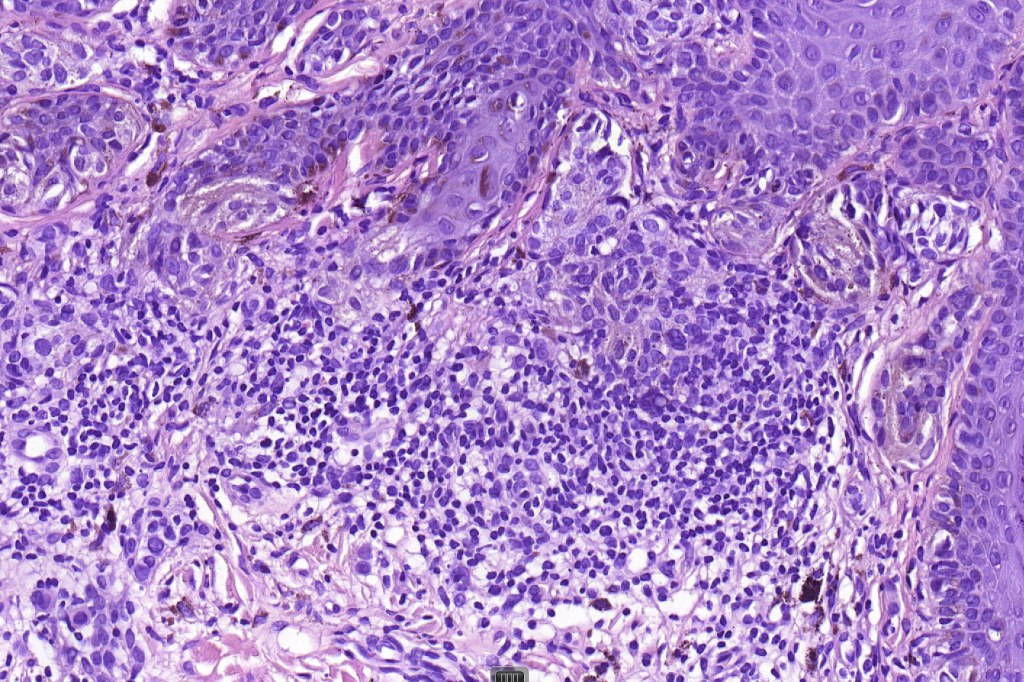

•Hyperkeratosis, & acanthosis sometimes present, otherwise epidermis of normal thickness

•Usually compound nevus with intense infiltration by lymphocytes, histiocytes and occasional plasma cells, in particularly florrid examples immunohistchemistry may be necessary to identify the nevus cells

. Sometimes prominent numbers of Langerhans cell

•Nevus cells often show degenerative atypia (nuclear pleomorphism, hyperchomatism & sometimes fine granular pigmentation (gray or gray/green)

•Melanophages present particularly in older lesions